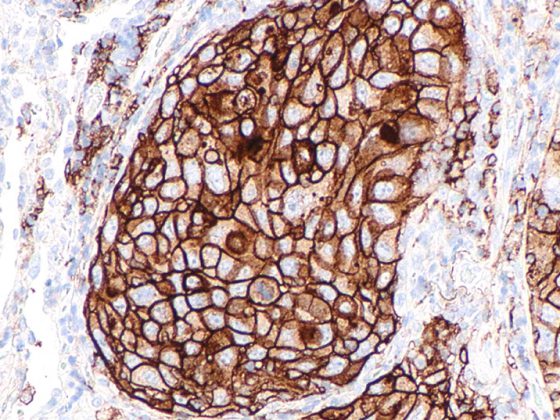

Das Nierenzellkarzinom (RCC) zählt zu den aggressivsten urologischen Tumoren weltweit. Trotz deutlicher Fortschritte in der molekularen Charakterisierung und Therapie bleibt die Erkrankung durch späte Diagnosestellung, komplexe Pathomechanismen und eine hohe Rate an Therapieresistenzen klinisch herausfordernd. Neue Einsichten in Genetik, Metabolismus, Immuninteraktion und Tumormikroumgebung haben nicht nur unser Verständnis der Pathophysiologie vertieft, sondern auch den Weg für innovative, personalisierte Therapien geebnet.